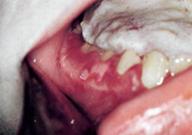

Рис. 196. Сыпь на небе. При поражении тройничного ганглия сыпь может появиться на слизистой